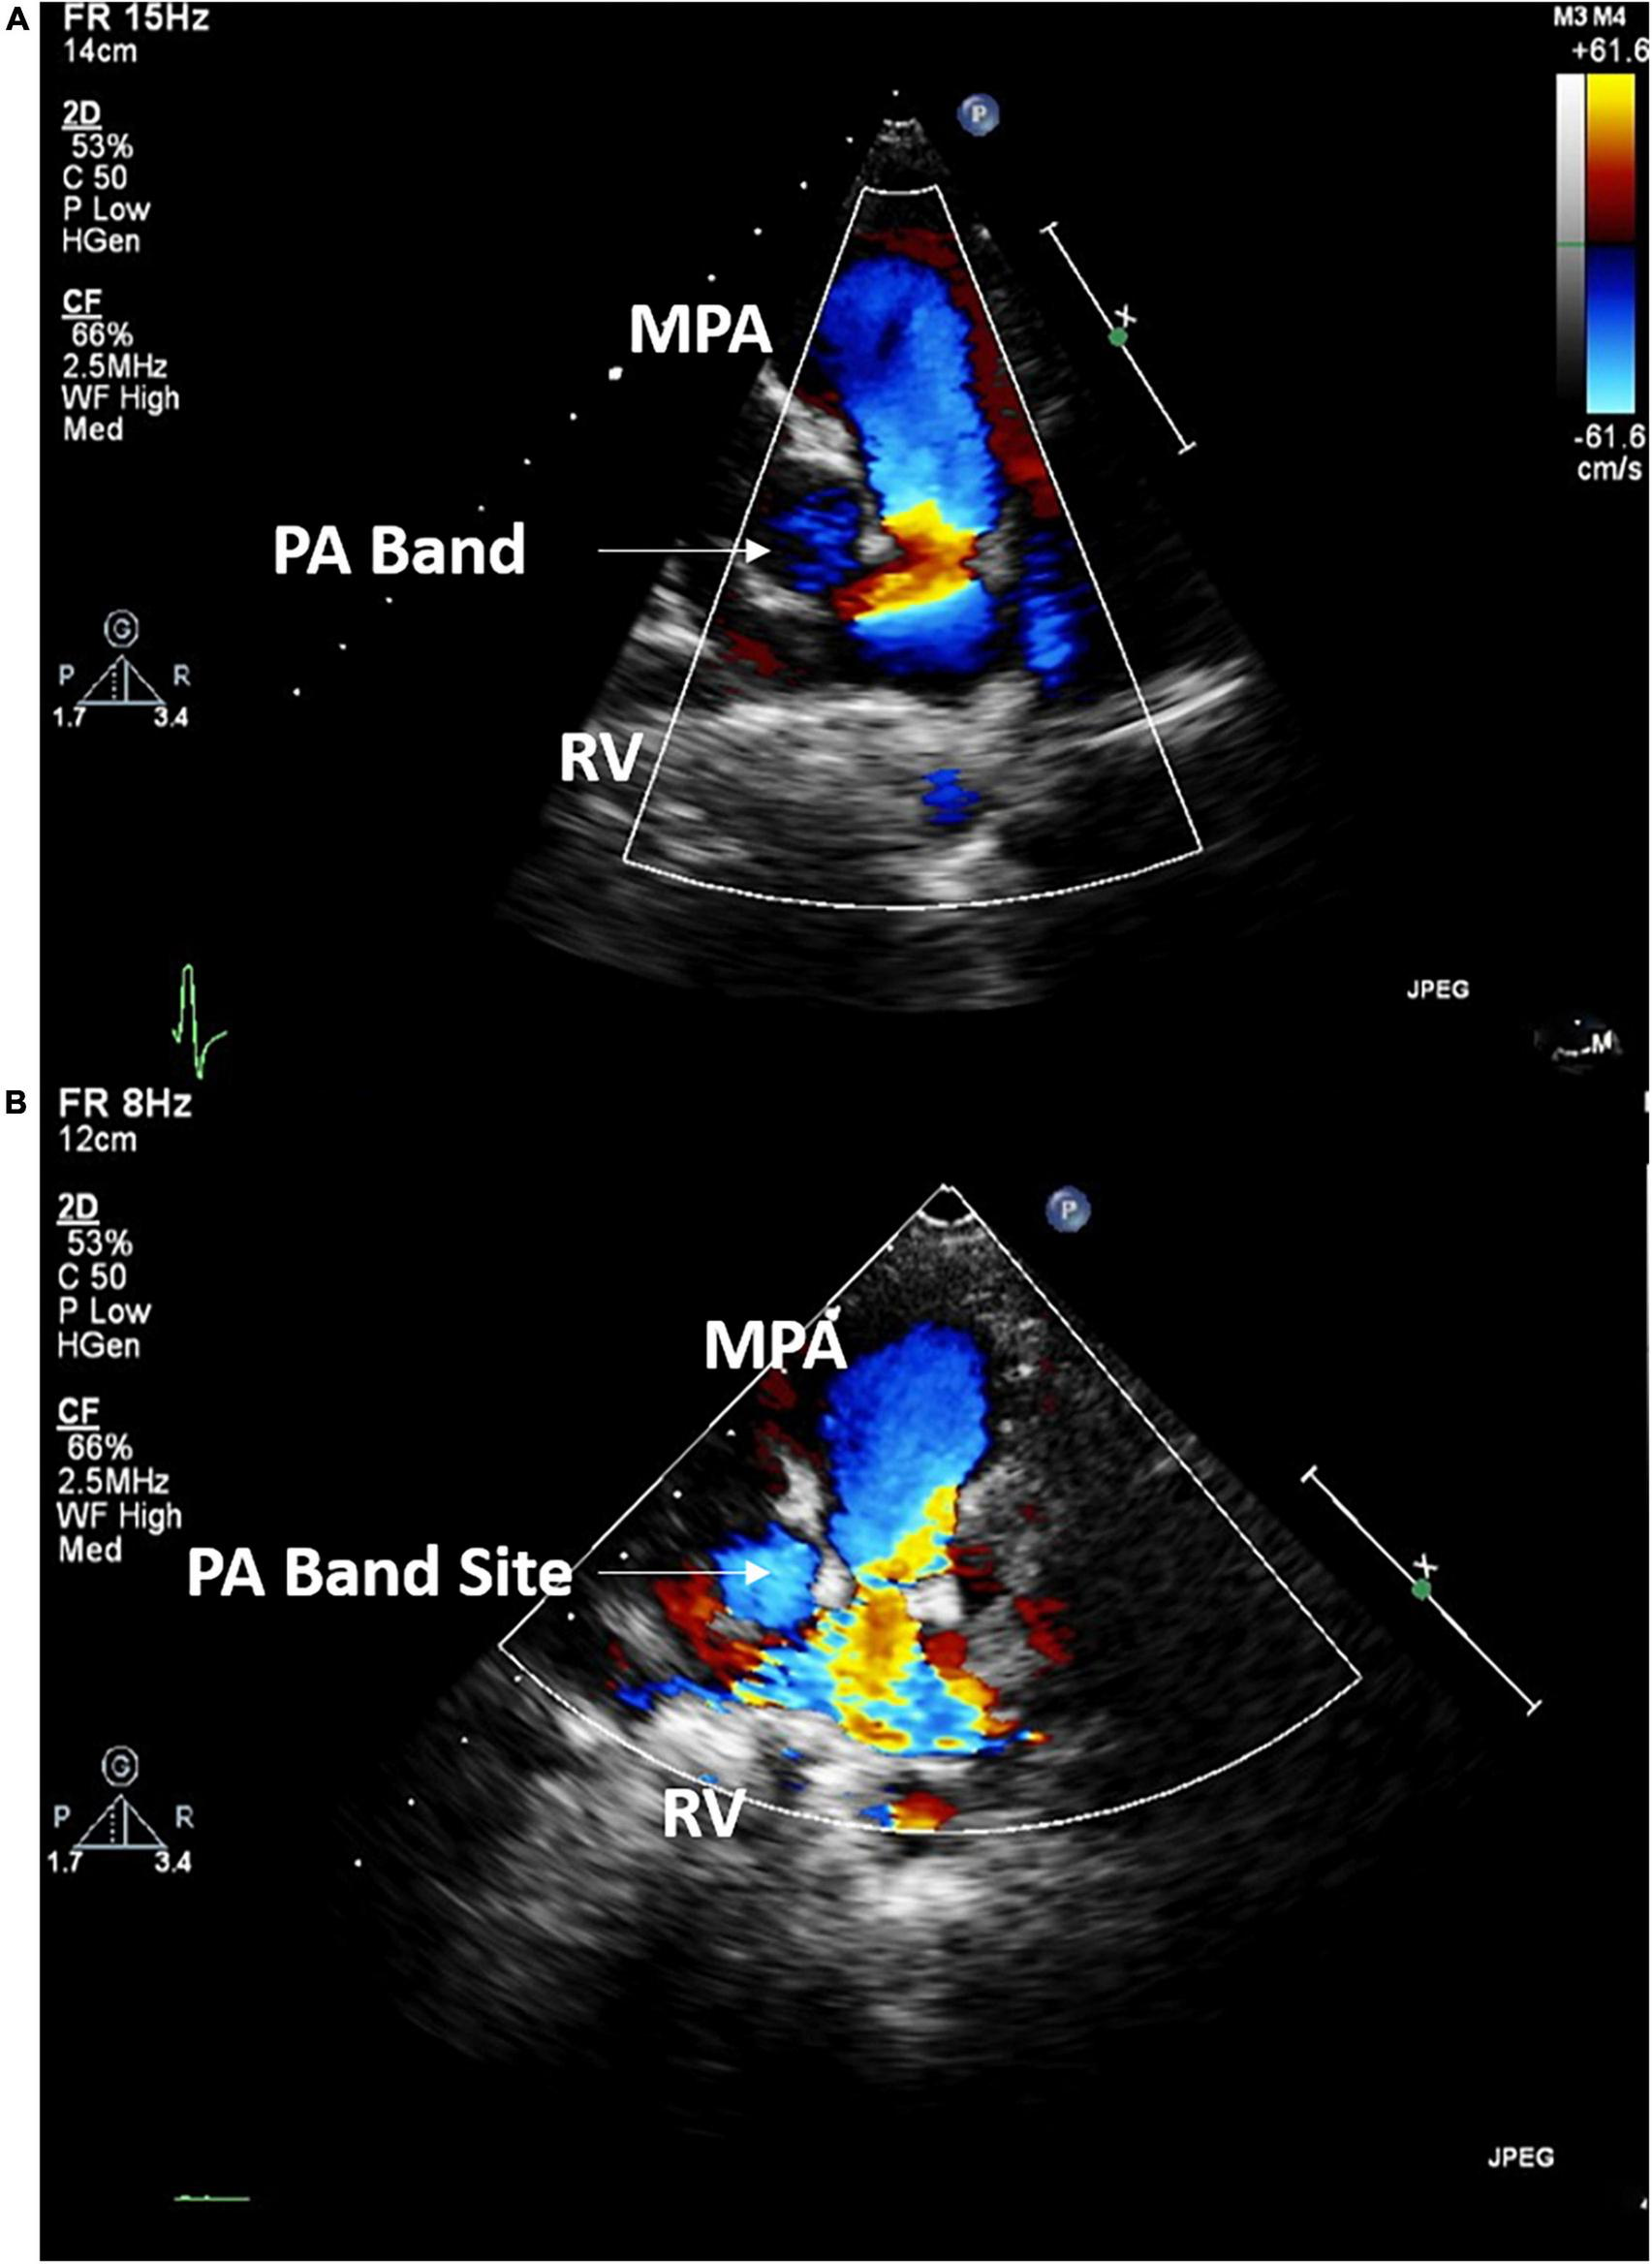

Case I: The first case of balloon dilation is a female patient who was diagnosed at birth with a large smooth muscular VSD measuring 13.5 mm in diameter and 7 mm in length. She had a PAB placed at the age of 2 months due to pulmonary overflow. At the age of 33 months, she presented for device VSD closure. Successful closure using a 16 mm amplatzer device was performed under general anesthesia without complications. Following the procedure, the right ventricular (RV) systolic pressure was measured at 85 mmHg, left ventricular (LV) systolic pressure was 95 mmHg, and the pressure gradient across the PA band was 60 mmHg. Three days later, balloon-based removal of the PA band was successfully performed under sedation, using 14 mm balloon (Figure 3). Pressure measurement following the procedure revealed: RV systolic pressure of 48 mmHg, and PA systolic pressure of 26 mmHg with a residual gradient of 22 mmHg across the band site. The patient tolerated the procedure well without complications and was pain-free by the second day following the operation, according to the Face, Legs, Activity, Cry, Consolability (FLACC) scale. She was followed up annually and when needed at the pediatric cardiology outpatient department via clinical and echocardiographic evaluation for 3 years following the percutaneous band removal; thereafter she was lost to follow up. At the last clinic visit, the patient was gaining weight adequately (weight = 20 Kg) and her systemic oxygen saturation was 100%. Her last echocardiographic imaging, at 3 years post-debanding, showed normal LV size and function, normal size of the main pulmonary artery, and an estimated RV systolic pressure of around 36 mm Hg. The patient was not maintained on any cardiac medications. Figure 4 shows the echocardiographic findings of the patient before the debanding procedure and at 3-year follow-up post debanding.

FIGURE 4

Echocardiographic imaging of Case I before (A) the debanding procedure and at 3-year follow up following the catheter-based debanding (B). RV, right ventricle; MPA, Main pulmonary artery; PA, Pulmonary artery.